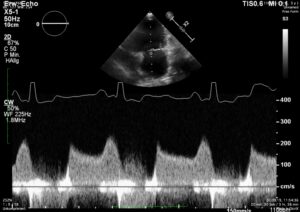

How would you diff b/w reverse remodelling and MV stenosis. Presented at recheck with mod severe pulmonary HT. Smll dog treated for chronic MVD stage C. US= LV under loading, FS > 50%, LAE remains significant. M e-vel is consistently 1.5m/s or higher but dec. time and press half time appear normal. E:A ratio around 1. Would LAE remain with aggressive medical Tx for MVD due to LA remodelling, LA compliance ,chronicity of MVD and ongoing reg. vol. compared to potential for LV to undergo reverse remodelling with Tx. Is stenosis seen much in min breed old dogs? Ls7 vid=2024. Tks!!

I see MS at all ages, because it is frequently missed in young dogs. But this case is not a MS. It is diagnosed as a combination of 2D-echo findings and the typical Minflow profile (E-wave very high frequently >2 m/s) confluent with A-wave. See image and video.